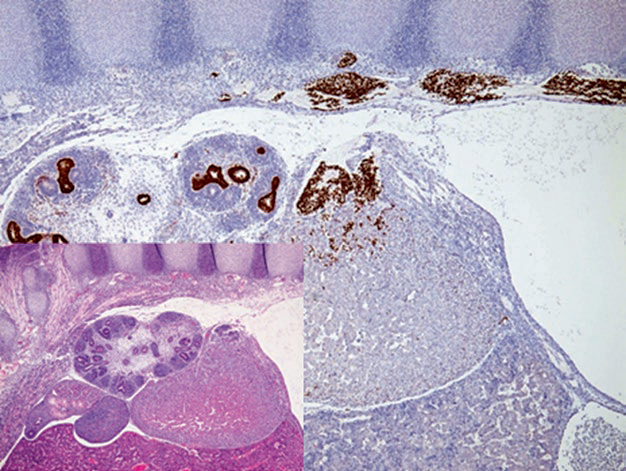

图片

图4. 12周胚胎组织切片,免疫组化GATA-3标记椎旁神经嵴中的交感神经母细胞。这些细胞会迁徙入原始肾上腺的背内侧、形成肾上腺髓质;GATA-3还可标记肾脏集合系统中的尿路上皮。

图5. 嗜铬细胞瘤,瘤细胞的胞核表达GATA-3。